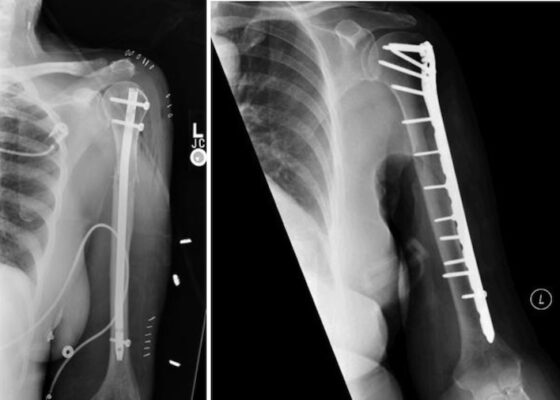

Phẫu thuật

- Xử trí ban đầu sẽ bao gồm mổ hở nắn chỉnh bằng nẹp cố định hoặc đinh nội tuỷ sau đó là nẹp chức năng Sarmiento 10 đến 12 ngày sau chấn thương ban đầu.

- Các chỉ định phẫu thuật tuyệt đối cho gãy thân xương cánh tay bao gồm gãy hở, chấn thương mạch máu cần sửa chữa, chấn thương đám rối thần kinh cánh tay, gãy xương cẳng tay cùng bên và hội chứng chèn ép khoang.

Phần lớn các trường hợp (90%) gãy thân xương cánh tay có thể được điều trị không cần phẫu thuật bằng bó bột hoặc đeo nẹp. Phần còn lại có thể cần điều trị phẫu thuật như cố định trong hoặc đóng đinh nội tủy.